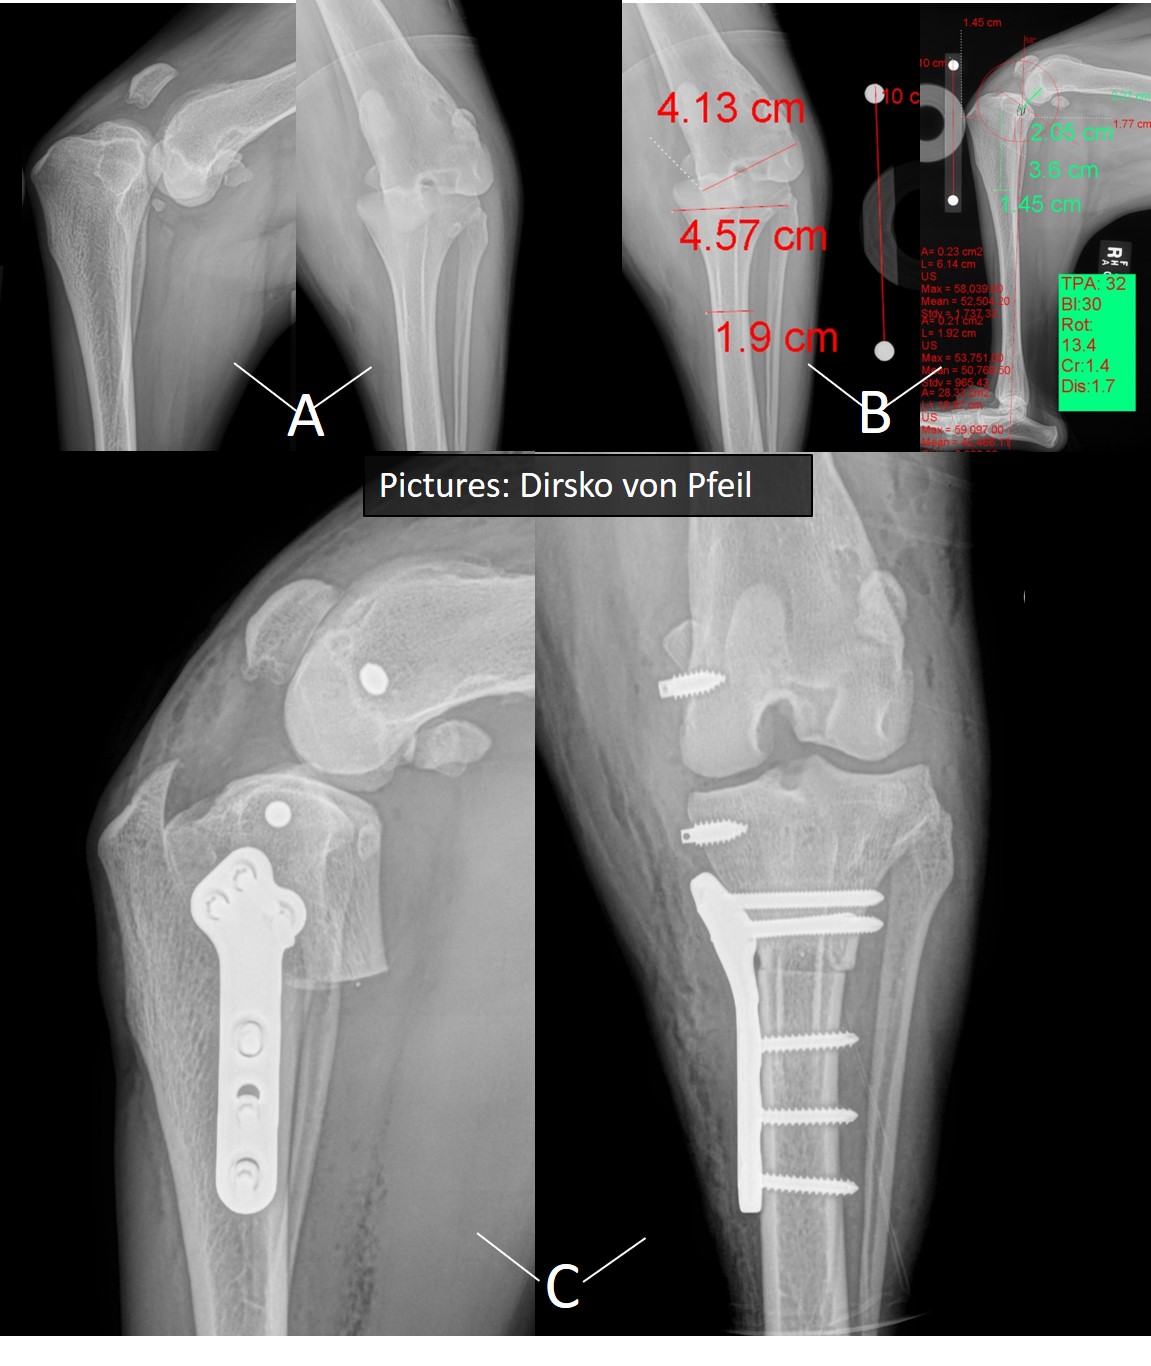

Luxation der Kniescheibe

Luxation der Kniescheibe(Kniescheibenverrenkung / Kniescheibenluxation)

Hierbei springt die Kniescheibe aus der vorgesehen Gleitbahn nach aussen heraus. Verschiedene Techniken, basierend auf Schweregrad des Problems, werden ergriffen, um die Kniescheibenverrenkung / Kniescheibenluxation zu beheben.

Computertomographie zur Beurteilung einer abnormen distalen Femurwinkelung, dem unteren Teil des Oberschenkels (A) die zur Luxation der Kniescheibe (Patella) führte, und Planung der korrigierenden Operation (B,C). Intraoperative Ansicht (D) und Röntgenbild nach der Operation (E). Nach der Operation ist der Oberschenkelknochen gerade ist und die Kniescheibe stabil.